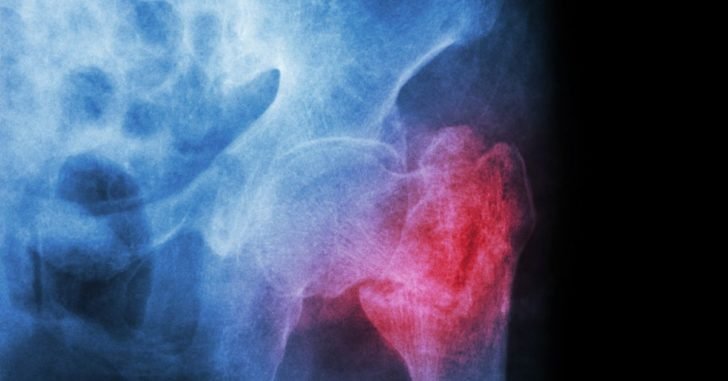

People commonly receive cortisone injections to treat joint pain and osteoarthritis. But a study has found that these shots may have dangerous side effects.